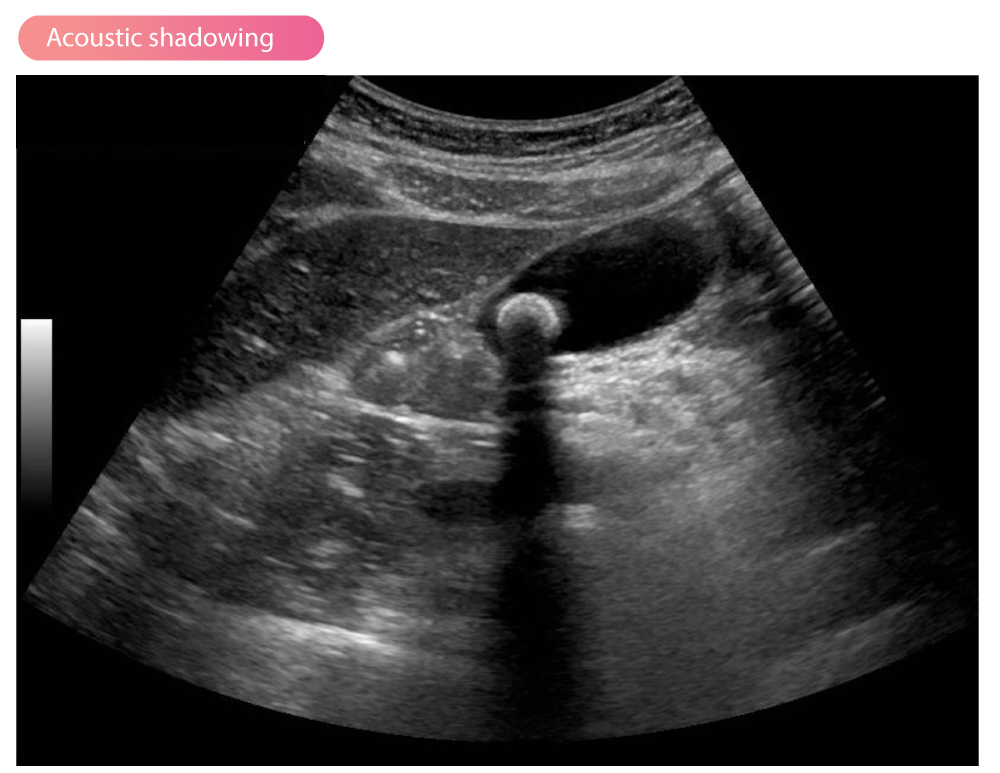

ID this artifact

Acoustic Shadowing